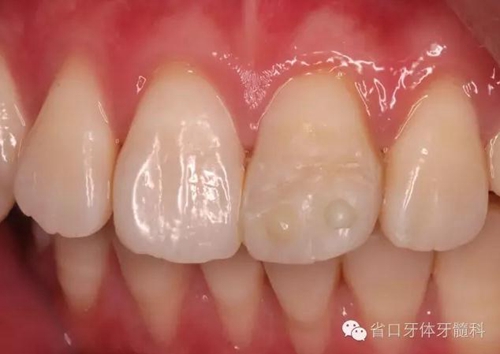

術(shù)前口內(nèi)照

口內(nèi)檢查:21切1/3-1/2折斷,髓腔暴露,探痛明顯

近中鄰面探及齲損,松-,叩+,齦緣輕度紅腫,探及齦下結(jié)石。

口內(nèi)檢查:21切端牙體色澤恢復(fù),唇側(cè)面見水平向粘接界面,殘留少許樹脂水門汀,牙齦腫脹較前消退,叩-,松-。

術(shù)后即刻口內(nèi)照